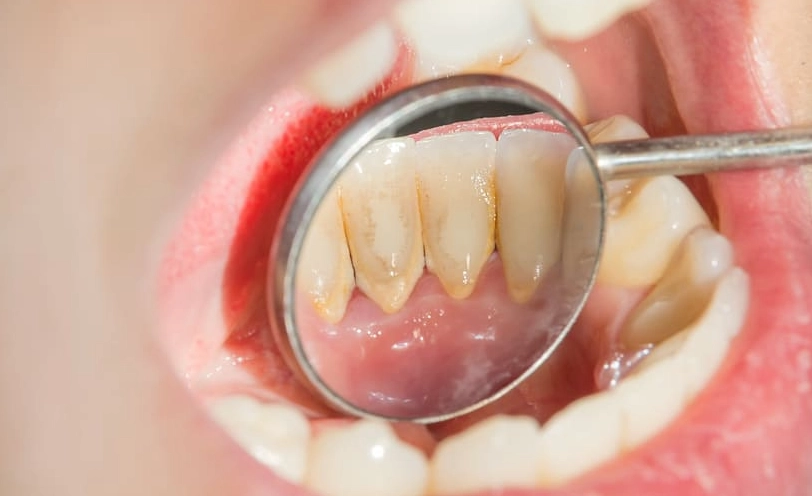

你可以把牙菌斑想像成一個由細菌、食物殘渣和唾液組成的黏性薄膜,它無色或淡黃色,緊緊貼在牙齒表面,尤其是牙齦溝和牙縫這些牙刷很難徹底清潔的地方。它不是吃飽飯馬上出現,而是大約飯後4到12小時開始形成。

最麻煩的一點是,如果沒有及時清除,牙菌斑裡的細菌會分解食物中的糖分,產生酸性物質。這些酸會腐蝕牙齒琺瑯質,蛀牙就來了。同時,牙菌斑如果堆積在牙齦邊緣,會刺激牙齦發炎,紅腫流血,這就是牙齦炎。再放任下去,發炎往牙根深處走,破壞牙周組織,變成牙周病,牙齒就可能開始搖動。

我常跟病人說一個比喻:牙菌斑就像浴室磁磚縫的皂垢,每天輕輕刷洗很容易掉,但放著不管幾天,它就會硬化成頑固的污漬(變成牙結石),這時非得用專業工具(洗牙)才清得掉了。